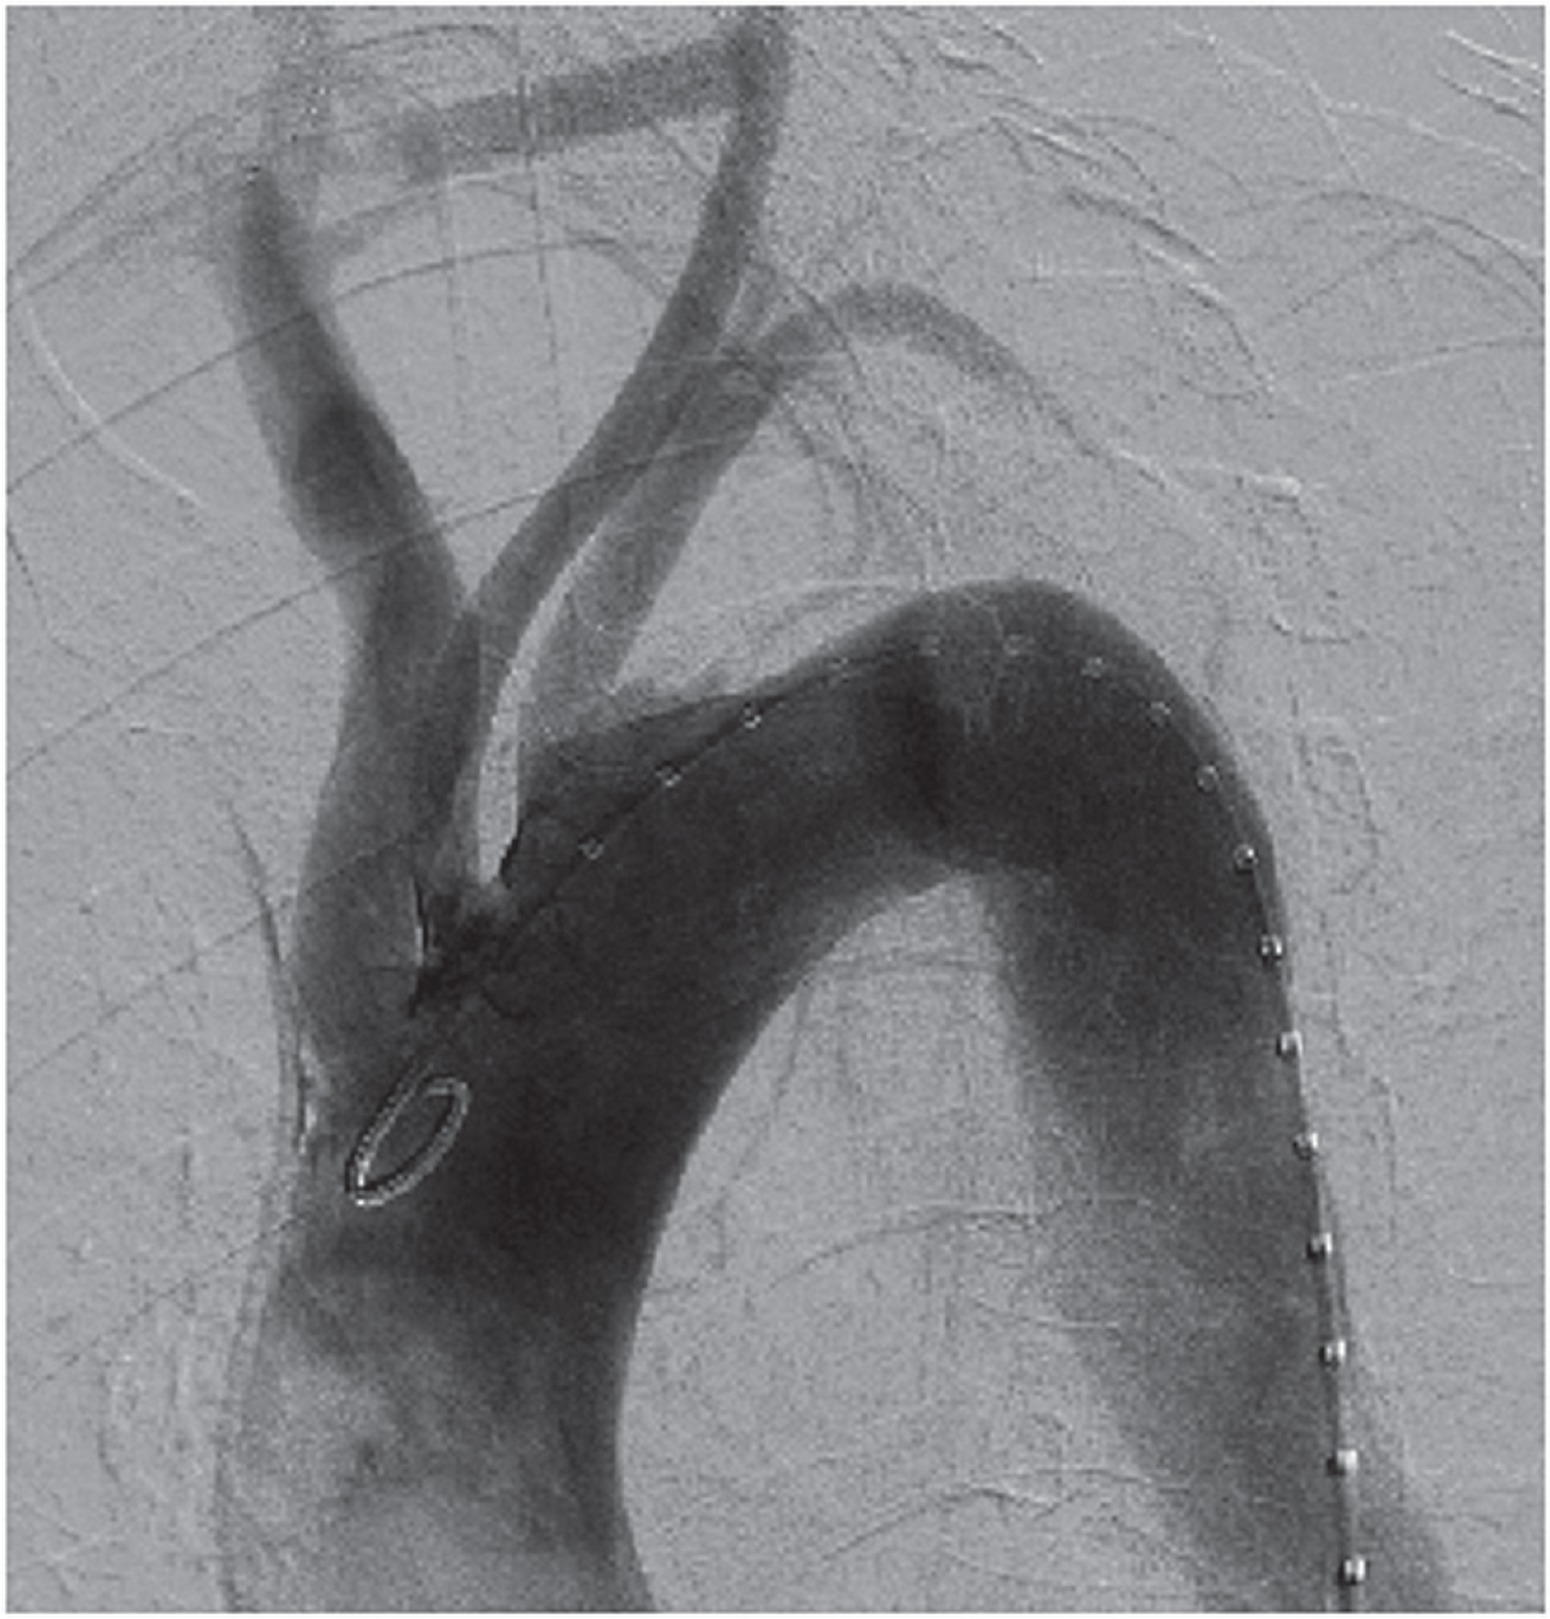

The carotico-carotid bypass preceded the endovascular stent placement. End-to-side 8 mm PTFE grafts were anastomosed to the right and left carotid artery using 6-0 prolene suture with partial cross clamp. Neurological status was monitored throughout the procedure with the Symantec monitoring system. Following the completion of the carotico-carotid bypass the left subclavian artery was coiled with 1 × 20 mm × 8 cm and 2 × 14 mm × 8 cm Nestor coils to prevent future leaks. A Cook Zenith TX -2 thoracic endograft (36/20-2 mm) was implanted in the descending thoracic aorta with the proximal landing zone extending to the origin of the left subclavian artery. Procedural CT angio showed a satisfactory position of the endovascular stent and no endoleaks. Also the carotico-carotid bypass was confirmed to be patent (Fig. 2).

Fig. 2

Computed tomography angiogram confirming absence of endoleak and patent carotico-carotid bypass